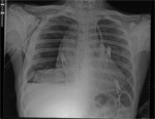

The most common symptoms were cough, chest pain, fever, and dyspnea. The most common physical finding was decreased breathing sounds at the affected hemi-thorax. There were signs of cyst perforation of the bronchial space in 14 patients. The cysts were ruptured to the pleural space in 5 patients, with pleural effusion or localized empyema; 4 of them required decortication due to air trapping in the lung. The cyst was found to be intact but infected in 1 patient with cardiac cyst. Cystotomy plus capitonnage was the most frequently used surgical procedure, which was performed in 18 patients, while lobectomy was performed in 1 patient, and left ventriculotomy plus cystotomy plus capitonnage was performed in 1 patient.